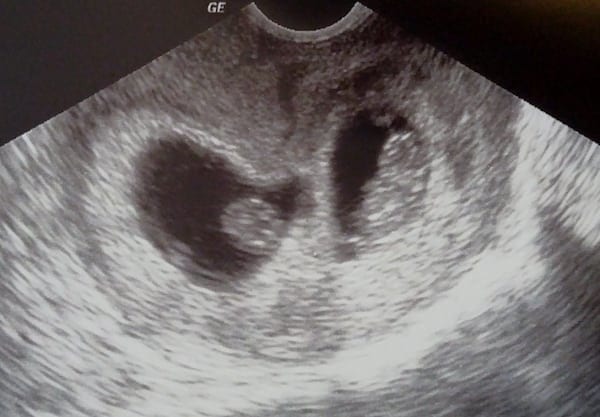

Ultrasound Photos – 8 Week Sonogram

8 week sonogra